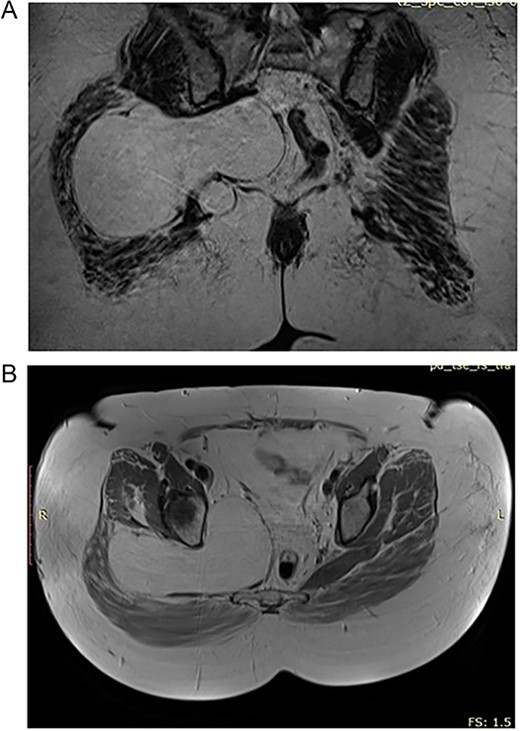

(A) Transgluteal approach used for excision of the lipomatosus lesion. (B) Complete resection of the lesions and intraoperative measurement of its sizes.

This technique facilitated the en bloc removal of the capsule along an extracapsular plane, a critical step in achieving the complete resection of the lesion (Fig. 3B).

Histopathological evaluations confirmed a benign lipoma with localized high fibrous tissue and fat necrosis. No signs of malignancy were identified.